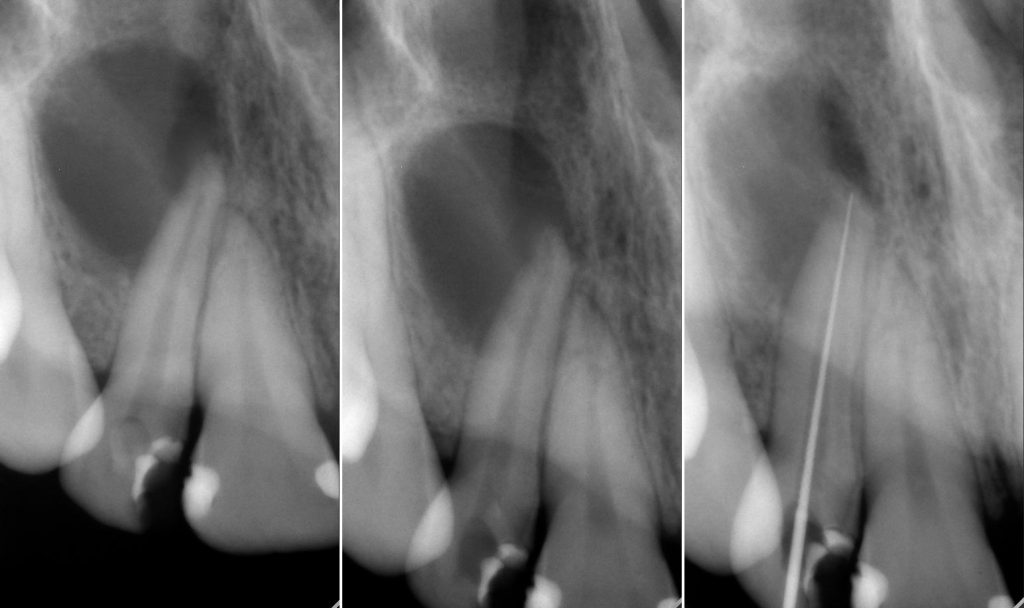

Streszczenie: Praca przedstawia przebieg leczenia endodontycznego górnego prawego bocznego zęba siecznego. Objawy kliniczne i wykonana diagnostyka radiologiczna wskazywały na istnienie przewlekłego zaostrzonego zapalenia tkanek okołowierzchołkowych. Ze względu na rozległość zniszczenia tkanki kostnej brano pod uwagę konieczność przeprowadzenia leczenia chirurgicznego. Przypadek ten jest jednak przykładem, że leczenie kanałowe jako zachowawcze, niechirurgiczne postępowanie może prowadzić do gojenia się rozległej zmiany okołowierzchołkowej.

Summary: The article aims to report the endodontic treatment of an upper right lateral incisor. The clinical symptoms and radiological diagnosis pointed at exacerbated chronic apical periodontitis. Due to the extensiveness of bone loss, a complementary surgical intervention was considered. This case report shows that a root canal treatment as a conservative, nonsurgical approach may lead to the appropriate healing of large lesions.